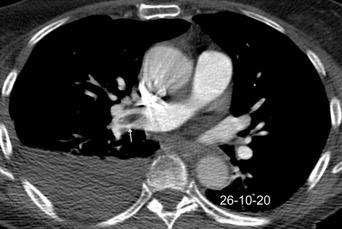

Tromboembolismo pulmonar.

Frecuencia del derrame:

Rx: 32%. TC: 47%

Unilateral. 85%

< 1/3 del hemitórax: 90%

Todos exudados

58% con eritrocitos

21% tabicación lo que causa demora en el diagnóstico

TEP. Empiema pleural. Atelectasia redonda

Porcel JM et al. Analysis of pleural effusions in acute pulmonary embolism: radiological and pleural fluid data from 230 patients. Respirology 2007/ Iguchi T et al. Desquamation of the subpleural lung parenchyma caused by empyema after pulmonary embolism: A case report. Respirol Case Rep. 2022 .